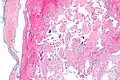

Pathology

Histopathology Images